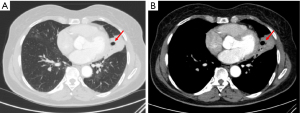

The key distinction in the differential diagnosis of cavitary lung lesions is between malignant and nonmalignant causes (8). Primary lung cancer is a common condition, with cavitation seen in 7% to 11% of cases on plain radiographs and up to 22% on CT (8). Cavitation is more commonly associated with squamous cell carcinomas than other histological types and is linked to a worse prognosis (Figures 1,2) (8). Other primary lung tumors, such as lymphoma and Kaposi’s sarcoma, may also present with cavitary lesions, particularly in individuals infected with human immunodeficiency virus (HIV) (8). Cavitary lesions were noted in CT scans of HIV-positive patients with primary pulmonary lymphoma (8). Lymphomatoid granulomatosis, a rare malignant disorder associated with Epstein-Barr virus, often presents with pulmonary cavities and may be mistaken for a lung abscess (8).

Malignancy is a common consideration for solitary cavitary lung lesions in middle-aged or elderly individuals with a history of smoking (4,7,9). In fact, the most frequently found solitary cavitary nodule in the lungs is a malignant tumor (7). These nodules can appear in any part of the lungs, with typical imaging findings including irregular and thick walls exceeding 24 mm in thickness, along with the presence of perilesional consolidation (5,7,10,11).